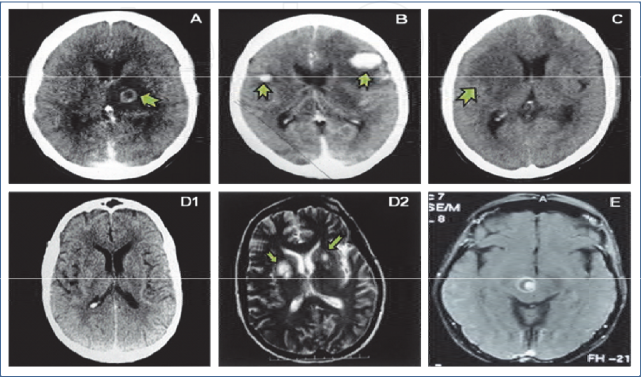

图注:大脑弓形虫塑造了人的性格

举一个简单的例子,感染人类大脑的弓形虫。这种寄生虫在人群中的感染率为20%~60%,有些地区甚至高达95%。

一旦被感染,它将伴随你终身,却不会让你有任何的不适感,只是现在越来的越多的研究表明这货可以塑造你的性格,让你变得暴躁(据信感染者出车祸的概率是未感染者的6倍)。